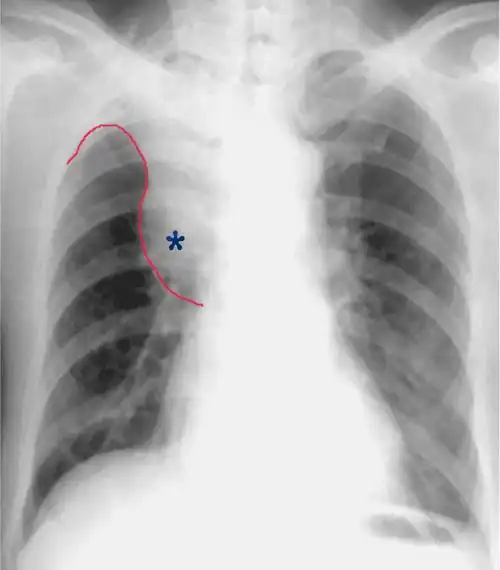

中央型肺癌的横s或者反s征,是指右侧中央型肺癌的正位x光胸片上的典型